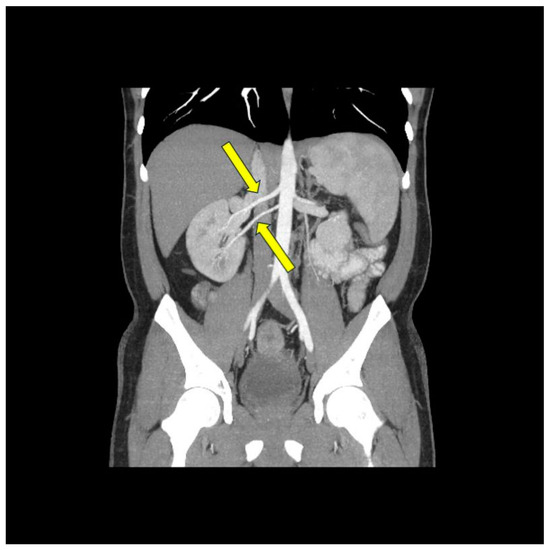

- Możeńska, O.; Rosiak, M.; Gziut, A.; Gil, R.J.; Kosior, D.A. First-in-man experience with renal denervation of multiple renal arteries in a patient with solitary kidney and resistant hypertension. Pol. Arch. Intern. Med. 2017, 127, 60–62. [Google Scholar] [CrossRef]

- Song, W.H.; Baik, J.; Choi, E.-K.; Lee, H.-Y.; Kim, H.H.; Park, S.-M.; Jeong, C.W. Quantitative analysis of renal arterial variations affecting the eligibility of catheter-based renal denervation using multi-detector computed tomography angiography. Sci. Rep. 2020, 10, 19720. [Google Scholar] [CrossRef] [PubMed]

- Tokarek, T.; Rajtar-Salwa, R.; Rzeszutko, Ł.; Bartuś, S. Long-term benefit of redo sympathetic renal denervation in a patient with resistant hypertension. Postep. Kardiol. Inter. 2021, 17, 239–241. [Google Scholar] [CrossRef] [PubMed]

- Atas, H.; Durmus, E.; Sunbul, M.; Mutlu, B. Successful accessory renal artery denervation in a patient with resistant hypertension. Heart Views 2014, 15, 19–21. [Google Scholar] [PubMed]

- Bertoldi, L.; Latib, A.; Piraino, D.; Regazzoli, D.; Sticchi, A.; Pizzetti, G.; Camici, P.G.; Colombo, A. Renal denervation in a patient with two renal accessory arteries: A case report. Blood Press 2013, 22, 325–328. [Google Scholar] [CrossRef] [PubMed]